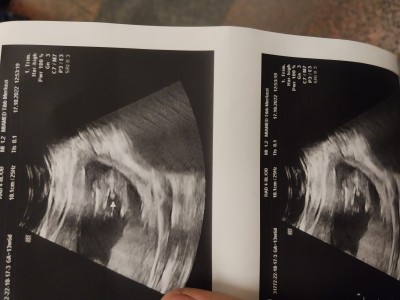

14 15 haftalik hamilelik doktor erkek dedi sizce ne

Gebelik haftası 15

Erkek canım okadar brlliki sağlıkla gelsin sormana gerek bile yok :))

Erkek canim bu kadar belirgin olamazdı darısı bana inşallah bı kızım var bu erkek olsun istiyorum dua edin banada henüz 12+2 feyiz çok kısa süre içinde öğreniriz artik

Kız gormuyon mu erkeğim diye bağırıyor tosuncuk:)

Nett erkekkk masallahhh